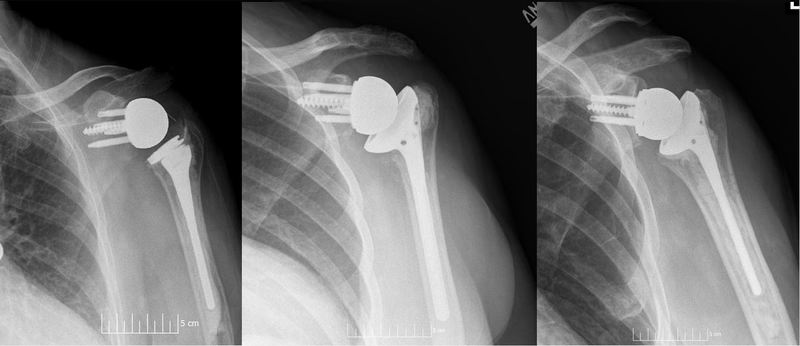

While studies often identify obesity as a potential risk factor for complications following total shoulder arthroplasty (TSA), few have looked at outcomes for patients who are underweight. “Overweight patients are frequently delayed or denied from surgery due to their weight,” said Jonathan Grauer, MD, Professor and Interim Chair, Department of Orthopaedics and Rehabilitation at Yale School of Medicine. “In the past, literature has predominantly stated that overweight patients are at risk of adverse outcomes, however, more recently studies have started to state a more mixed picture. Although there are many studies investigating the effect of obesity on outcomes, underweight patients on the other end of the BMI spectrum are often not considered in these studies and have largely been underrepresented.”

The study, “Underweight Patients are the Greatest Risk Body Mass Index Group for Perioperative Adverse Events Following Total Shoulder Arthroplasty,” looked at a total of 15,725 patients undergoing elective TSA who were pulled from the National Surgical Quality Improvement Program database. Patients were put into BMI categories according to the World Health Organization: underweight (BMI < 18.5 kg/m2), normal weight (BMI of 18.5 to 24.9 kg/m2), overweight (BMI 25.0 to 29.9 kg/m2), obese (BMI of greater than 30.0 to 39.9 kg/m2), morbidly obese (BMI of greater than 40.0 to 49.9 kg/m2), and super morbidly obese (BMI greater than 50.0 kg/m2).